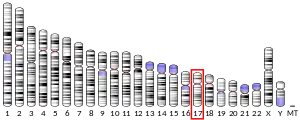

Genetics

The gene for G-CSF is located on chromosome 17, locus q11.2-q12. Nagata et al. found that the GCSF gene has four introns, and that two different polypeptides are synthesized from the same gene by differential splicing of mRNA.[10]

The two polypeptides differ by the presence or absence of three amino acids. Expression studies indicate that both have authentic GCSF activity.